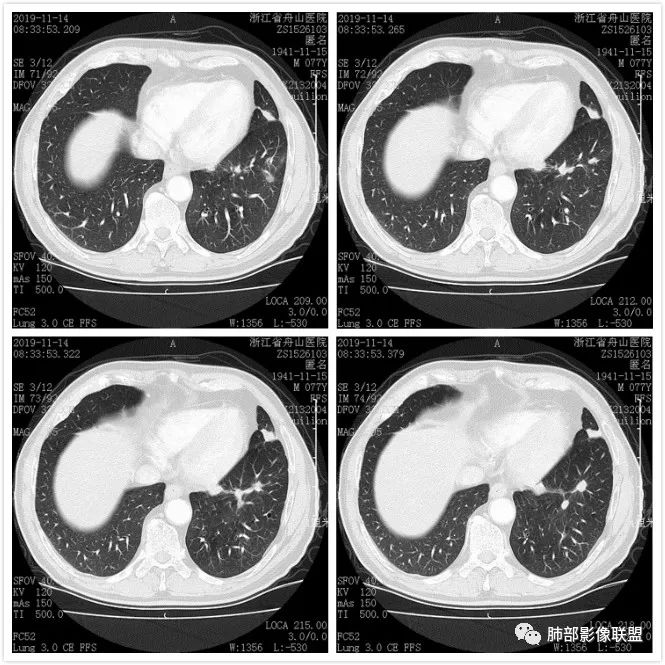

真假支气管爬行征—肺腺癌1例CT影像讨论

影像资料

总结

这个病例似乎是外头大内头小,由外围往内蔓延,和我们常讲的结核的支气管爬行征有类似地方。 医学百科网 | YxBaike.Com

那么它到底是不是结核肉芽肿呢?我们先来复习下支气管树爬行征的影像应该同时符合以下四条:1.近端支气管通畅,2.病侧肺容积正常,3.外周朝内侧生长,4.外宽内窄逐渐“爬行”向肺门。 医学百科网 | YxBaike.Com

那么我们对照来看到底符不符合呢?首先这个病例近段支气管是鼠尾样狭窄的,所以第一条就不能满足,况且此病灶还具有边缘膨隆,周边有细短毛刺,内不均匀强化,内血管破坏等恶性特点,所以此征不等同于肉芽肿型的爬行征,切不可以误用概念征象。

图一:可见支气管狭窄截断,图二,肿块内血管破坏,图三边缘膨隆毛刺